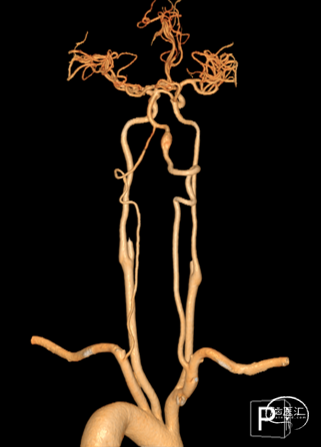

影像科提供的重建图像就像美颜照片,虽然好看,但丢失了诸多细节。

我们使用影像工作站重建的图像能够看到更多细节:

动脉瘤处有明显的凹陷,考虑为动脉夹层的内膜瓣;动脉瘤累及小脑后下动脉(PICA)的开口。

3D造影:动脉瘤处有明显的凹陷,符合夹层内膜瓣表现;PICA从动脉瘤远端发出,动脉瘤大小约6.5×12.8mm,受累椎动脉直径约4.3mm,覆盖远近端达正常血管约需30mm支架长度。